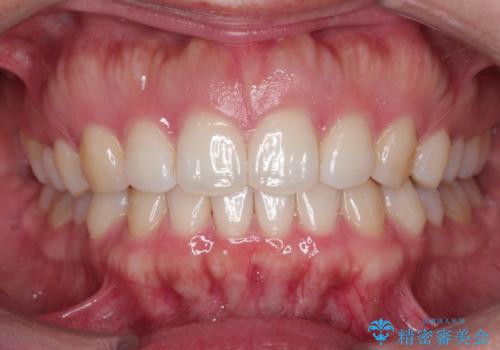

前歯のインプラント治療 折角なので矯正治療できれいな歯並びに